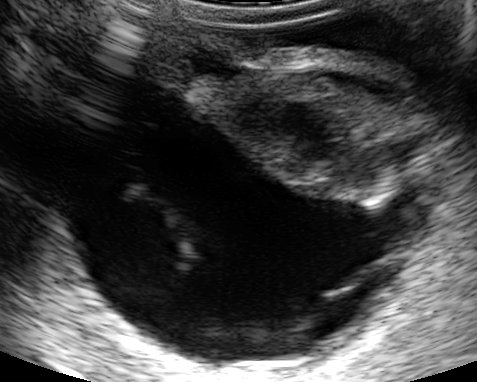

Figure 3: This ruptured lens has an irregular shape with a flattened posterior outline. Retinal detachment is also present.

Diabetic Cataracts in Dogs – The solution: Prompt referral

Currently the only effective way to deal with these cases is to remove the source of the inflammation: i.e. the cataractous lens. This is often a race against time and the urge to completely stabilise your diabetic patient prior to surgery. If lens capsule rupture has occurred they need to have their lenses removed urgently to avoid permanent blindness. If your diabetic patient suddenly develops mature cataracts and your owner is in a position to consider cataract surgery a prompt assessment by a veterinary ophthalmologist could save their vision. Treatment with NSAIDs (systemic and topical) prior to

surgery is desirable (2 to 7 days of treatment is ideal). As soon as any DM cataract is noted it is advisable to begin anti-inflammatory treatment (e.g. Ketorolac OU BID and Meloxicam PO SID).